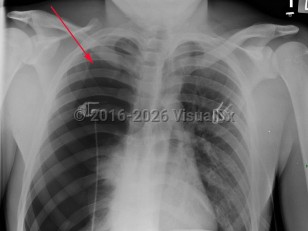

Chest pain, Dyspnea, 50-59 year old Female